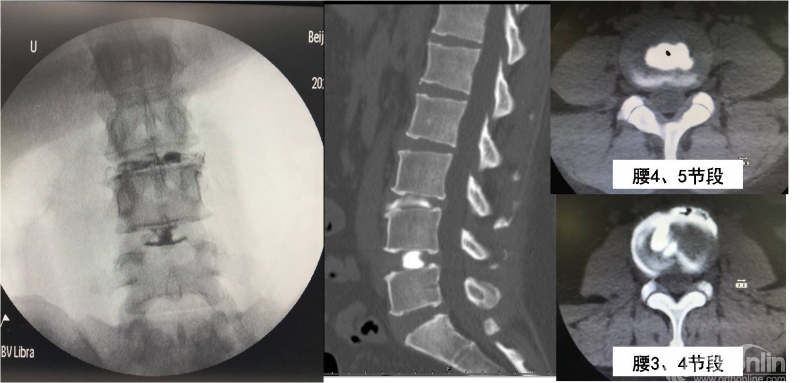

本例患者入院后首先接受了诱发性椎间盘造影。根据患者疼痛感的部位和影像学表现,我们初步判断腰3/4间盘为责任间盘,同时以腰4/5间盘为对照间盘。透视下首先进行腰4、5节段椎间盘造影未诱发出疼痛。再次行腰3、4节段椎间盘造影,患者自述出现与术前相同部位,相同性质,相同程度的腰腿痛症状。术后CT进一步证实腰3/4节段纤维环明显破裂,造影剂外渗,而腰4/5节段无上述表现。综合分析上述结果,认定该患者椎间盘源性腰痛诊断明确,责任节段为腰3/4间盘。

图2:椎间盘造影及CT可见腰4/5节段(右上)造影剂分部局限,无渗漏迹象,术中未诱发出疼痛;腰3/4节段(右下)造影剂外渗,并可诱发出明显疼痛